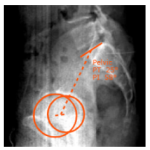

Estudio de la anatomía sagital de la pelvis de pacientes con dolor sacroilíaco en el ámbito laboral

Guillermo A. Ricciardi, Ignacio G. Garfinkel, Gabriel G. Carrioli, Daniel O. Ricciardi